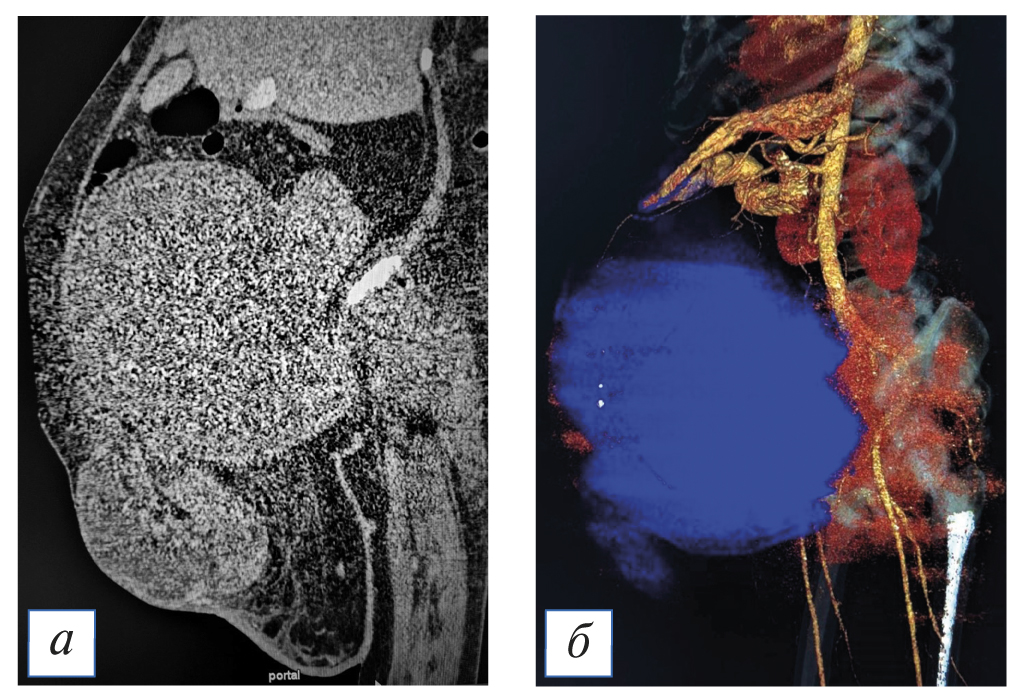

По данным ультразвукового исследования и компьютерной томографии органов брюшной полости и забрюшинного пространства с контрастным усилением: в проекции шейки и тела матки определяется объемное очаговое образование, гиперваскулярное, с бугристым контуром, размерами 35,2×26,4×11,4 см. Цервикальный канал, М-эхо, полость матки не дифференцируются (рис. 2). Яичники не визуализируются, в их проекции определяется образование кистозно-солидной структуры с множественными перегородками и отчетливой васкуляризацией по перегородкам, заполняющее всю брюшную полость (C-r яичников?). Асцит преимущественно в верхних отделах брюшной полости. Большой сальник утолщен, изменен в виде множественных гипоэхогенных мелкозернистых образований, максимальный размер узлов 7,5×6,4 см. Увеличены лимфатические узлы: парааортально — до 17 мм, по ходу общих подвздошных сосудов слева — 40×51 мм, справа — 28×31 мм. Определяется пупочная грыжа до 13,0 см в диаметре, в грыжевом мешке визуализируются измененный большой сальник, свободная жидкость.

Рис. 2. Результаты инструментального обследования: а — компьютерная томография органов брюшной полости; б — 3D-реконструкция по данным компьютерной томографии, в результате которой было оценено расположение опухоли по отношению к крупным сосудам брюшной полости. / Fig. 2. Results of instrumental examination: а — computed tomography of abdominal organs; б — 3D reconstruction according to computed tomography, as a result of which the location of the tumor in relation to large vessels of the abdominal cavity was estimated.

Заключение: Объемное образование малого таза, брюшной полости (из яичников?). Асцит. Поражение забрюшинных лимфатических узлов и большого сальника. Пупочная грыжа.